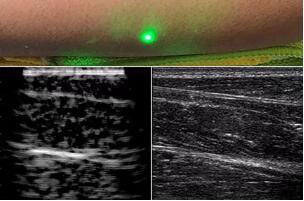

而麻省理工學院的研究小組現(xiàn)在開發(fā)了一種使用激光檢測皮膚上超聲波振動的方法,以便可以使用一種激光使皮膚產(chǎn)生共振,而另一種則可以檢測到振動,從而達到“遠程超聲掃描”的作用。

目前,研究人員已經(jīng)與健康的志愿者測試了他們的系統(tǒng):從半米遠處掃描了他們的前臂,并將這些結(jié)果與傳統(tǒng)超聲的結(jié)果進行了比較。他們能夠觀察到深達6厘米的組織,并能看到肌肉,脂肪和骨頭,并報告其結(jié)果可與標準超聲相媲美。

研究人員用一種激光裝置測試了這個想法,該裝置使用一個波長為1,550納米的脈沖激光來產(chǎn)生聲波,并使用第二個連續(xù)激光,調(diào)諧到相同的波長以遠程檢測反射的聲波。第二個激光器是靈敏的運動檢測器,可測量聲波從肌肉,脂肪和其他組織反射回來而引起的皮膚表面振動。反射的聲波產(chǎn)生的皮膚表面運動會導致激光頻率發(fā)生變化,這種變化可以測量。通過機械掃描人體上的激光,科學家可以獲取不同位置的數(shù)據(jù)并生成該區(qū)域的圖像。